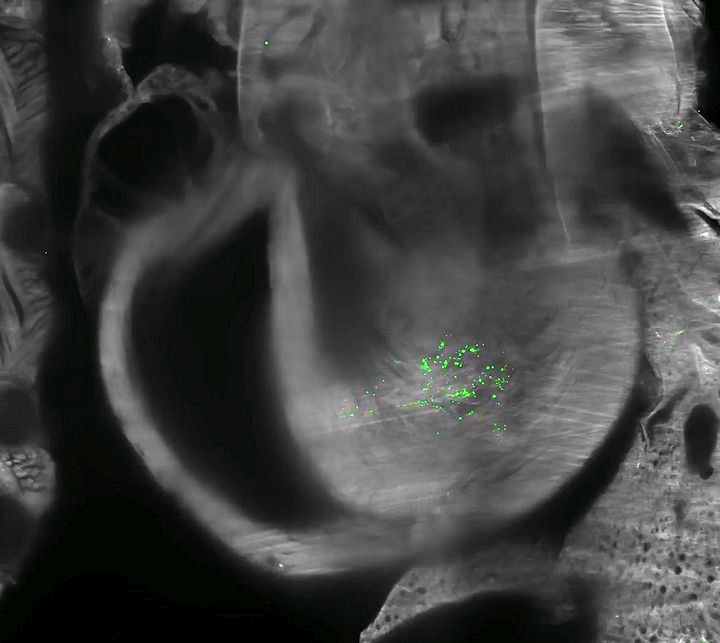

Zöld fluoreszcens fehérje (EGFP) expresszió egér szívében 72 órával kis adag, lipid nanorészecskékbe csomagolt EGFP mRNS-injekció beadása után

4. ábra: Lipid nanorészecskékkel bejuttatott mRNS-ből származó fehérje expressziója. Teljes test (a), lép (b), máj (c) és szív (d). f: az izomba beadott, lipid nanorészecskékkel bejuttatott mRNS-ből származó SARS-CoV-2 S1 tüskefehérje eloszlása a testben 72 órával az injekció beadása után. Tüskefehérjék a szívben (f′).

Luo, J., Molbay, M., Chen, Y. et al. Nanocarrier imaging at single-cell resolution across entire mouse bodies with deep learning. Nat Biotechnol (2025). https://doi.org/10.1038/s41587-024-02528-1. CC BY 4.0